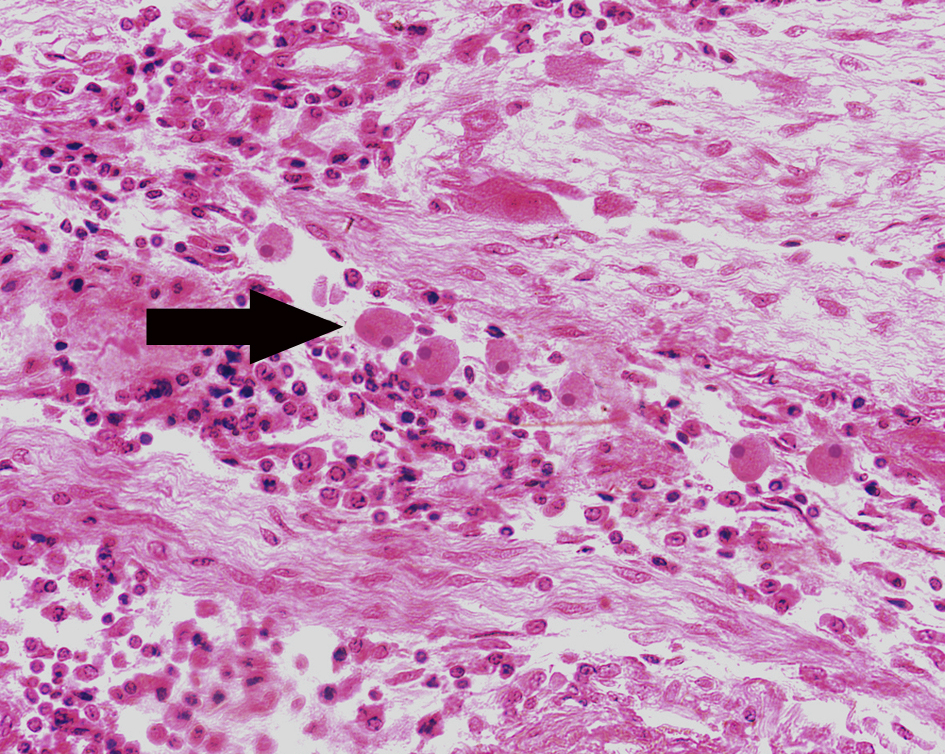

1.Amebic colitis

2.Schistosomiasis of the colon

3.Experimental acute schistosomiasis of the liver (rabbit)

4.Pile-stem liver fibrosis of schistosomiasis